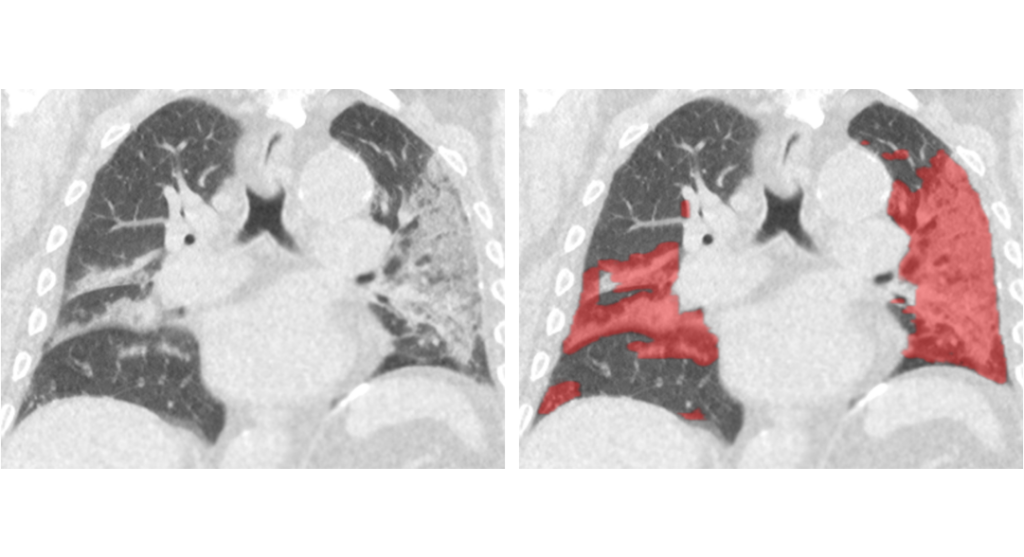

We have launched CAD4COVID-CT

We are proud to launch CAD4COVID-CT, our artificial intelligence software for the analysis of COVID-19 on CT scans.